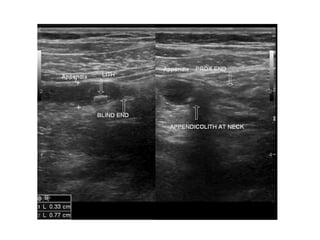

• Sonography

– appendix is identified as a blind-ending, nonperistaltic

– presence of an appendicolith establishes the

– Thickening of the appendiceal wall and the presence

– sensitivity of 55 to 96% and a specificity of 85 to 98%

Imaging • Sonography – inexpensive,can be performed rapidly, does not require a contrast medium, and can be used even in pregnant patients – appendix is identified as a blind-ending, nonperistaltic bowel loop originating from the cecum – presence of an appendicolith establishes the diagnosis – Thickening of the appendiceal wall and the presence of periappendiceal fluid is highly suggestive – sensitivity of 55 to 96% and a specificity of 85 to 98%